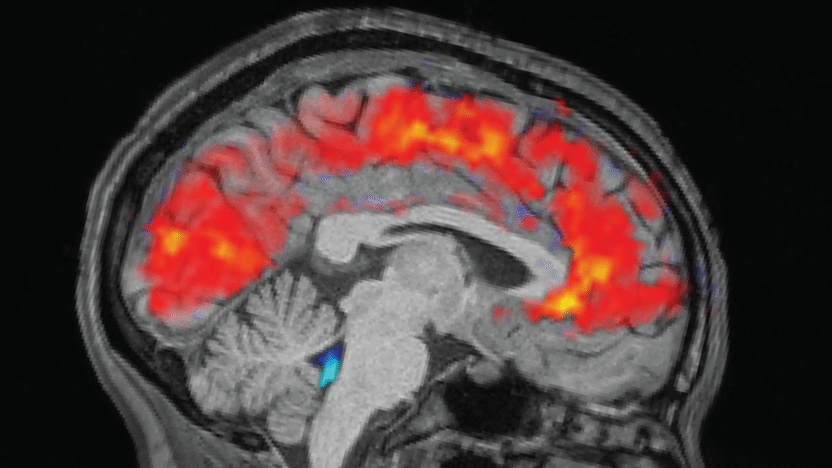

Scientists spot brains zoning out in real time

Ever get that feeling — say, at the end of the week — when you really want to pay attention to something important, but you just zone out and see people’s lips moving?

Well, scientists finally have a physiological explanation for why this happens when you’re sleep-deprived: Your brain is literally flushing out cerebrospinal fluid, making it nigh-impossible for you to concentrate. The exact functional reason for this is still unclear, but scientists think it could have something to do with sleep-deprived brains switching into sleep-like states, possibly as a form of waking brain waste disposal you missed out on the night before.